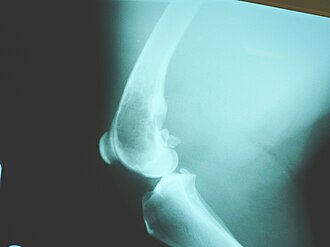

Dijagnoza obično počinje rtg-snimkom, pa zatim računalna tomografija (CT), scintigrafija kosti i na kraju potvrda tumora biopsijom. Na rtg-snimci može se vidjeti tzv. Codmanove trokut što ga čini ravnina vanjske strane kosti i izdignuta pokosinca (periost).